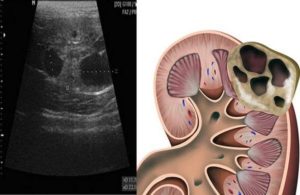

Паренхима образуется из:

- Корковых клеток

- Мозгового вещества

Киста паренхимы почки — тонкостенное круглое, овальное образование, заполненное жидким геморрагическим, серозным экссудатом с примесями гноя, крови. Параметры недуга — 3-10 сантиметров. Появляется новообразование с левой, правой сторон, передается по наследству. На левой, правой почках находят одновременно несколько кистом.

В паренхиме почки развитие кисты наблюдается при расширении нефронов и накоплении в них жидкости. Кистозная полость может иметь размер от 1 до 12 сантиметров. Врожденная киста иногда рассасывается самостоятельно, а при приобретенной необходима медицинская помощь.

- интрапаренхиматозная – формируется в толще функциональной ткани почек;

- синусная – локализована в области почечных ворот внутри или около синуса;

- субкапсулярная – возникает под фиброзной капсулой почки;

- кортикальная – находится в кортикальном (корковом) слое органа.

В половине случаев обнаруживается интрапаренхиматозная киста левой/правой почки. Она не закупоривает устье мочеточника и не препятствует оттоку мочи в мочевик. Поэтому интрапаренхиматозные кисты имеют наиболее доброкачественное течение.